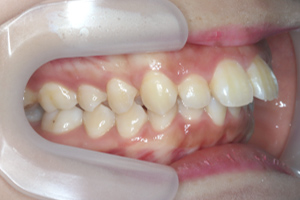

症例

矯正歯科専門の歯科医師が専門的な知識と確かな実績を

もとに患者様にあった最適な治療プランをご提案します。